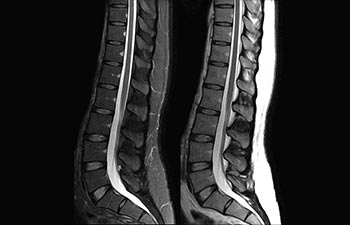

La Sra. Silvia Schiffer, directora y radióloga experta en la clínica Radiologie Schiffer, en Alemania, comparte sus experiencias con el sistema de RM Prodiva 1.5T.

Conozca la opinión de los primeros usuarios de Ingenia Prodiva 1.5T acerca de sus experiencias con el sistema y cómo influye este en su centro de diagnóstico por imagen.